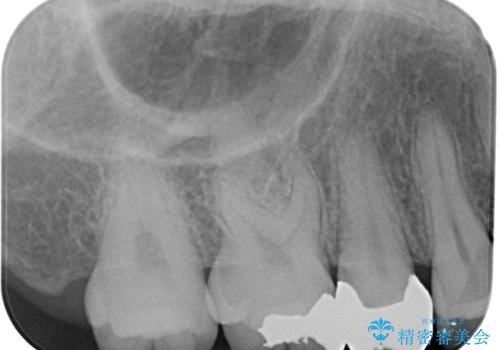

- 右上の銀歯を外したいとのことで来院された患者様です。検査後ハイブリッドインレーにて修復治療を行うことにしました。

拡大鏡視野下で銀歯、虫歯の除去を行い、ハイブリッドインレーに適した形に整えました。